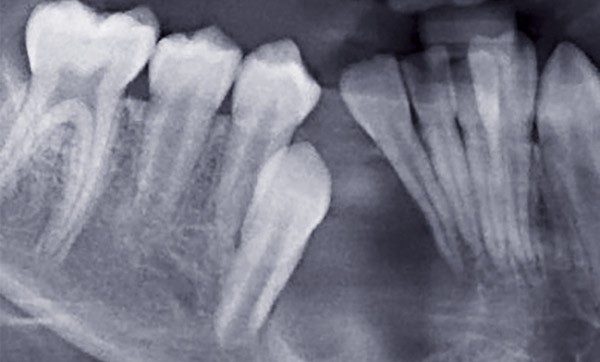

Devant tout retard d’éruption, il faut effectuer un bilan clinique et radiologique à la recherche d’une anomalie locale (kyste, odontome…) pouvant être un obstacle sur le chemin d’éruption. L’anamnèse médicale sera importante afin d’éliminer toute cause générale. Un avis orthodontique sera systématique.